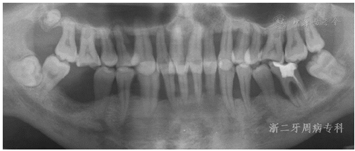

2009年4月:牙周基础治疗后1年复诊。患者口腔卫生可,牙龈色粉质韧,仅下前牙舌侧可见少量软垢,局部龈缘充血(图9),并惊喜地发现:下前牙31、41间隙已完全关闭。牙齿松动度、PD、BOP(+)%与半年前无明显变化(图10)。全口曲面体层X片示:牙槽嵴顶硬骨板较2007年12月清晰,14、17、24、34、36局部有牙槽骨修复、36根尖周骨密度增加,其余位点牙槽骨均未见进一步吸收;46缺牙区牙槽骨密度和高度增加(图11),提示牙周基础治疗后牙周状况得到了明显改善。因37、46缺失牙未及时修复,16略伸长,38近中倾斜,再次建议患者正畸治疗,直立38、压入16,排齐整平牙列,修复缺失牙37、46。患者拒绝正畸和修复治疗。予以16调磨、牙周维护治疗、35~44超级粘结剂牙周固定。

2011年4月:牙周基础治疗后3年复诊。患者口腔卫生维护佳,牙周状况良好,牙龈色粉,无明显红肿,口内未见明显结石与软垢(图13),牙齿松动度牙周袋进一步变浅,PD≥7 mm位点消失,4~6 mm的位点数进一步减少,仅有6个位点,BOP(+)%仅为6.5%(图14)。全口曲面体层X片示:牙槽骨硬骨板较明显,牙槽骨无进一步吸收迹象;37、46缺牙区牙槽骨高度无明显降低(图15)。检查结果显示,患者牙周状况已经稳定。予以牙周维护治疗、复发危险评估,评估结果为中度(图16),嘱患者继续保持口腔卫生,随访时间可延长至9~12个月。

2018年12月、2019年1月:牙周基础治疗后10年复诊。患者口腔卫生维护一般,口内可见少量龈上结石形成,部分牙龈充血肿胀,牙周探诊出血位点明显增多,牙周袋较2013年情况严重。牙周维护后,牙龈肿胀减轻,部分位点龈缘仍充血红肿(图18)。全口曲面体层X片示:与2011年4月比较,24近中牙槽骨再次出现角形吸收,36近中根牙槽骨进一步吸收;而全口其余位点牙槽骨没有明显出现进一步吸收现象,基本维持原有高度,37、46缺牙区牙槽骨高度无明显降低(图19)。PD 4~6 mm的位点数为85个,≥7 mm位点有7个,其中36舌侧远中牙周袋更是深达12 mm,全口BOP(+)%:26.8%(图20)。